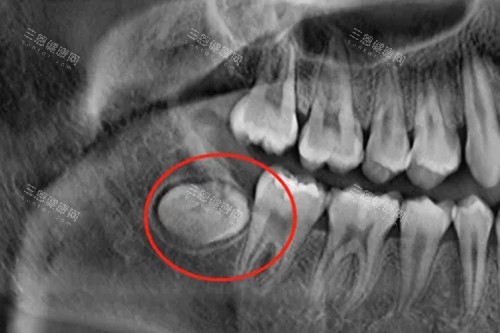

阻生智齿示意图

2. 完全埋伏、无症状的智齿

之前接诊过位30岁的患者,拍CT发现上颌有颗完全埋在骨头里的智齿,没发炎、不顶邻牙。

医生说:

“这种‘躺平’的智齿,定期观察就行,强行挖出来反而伤骨头。